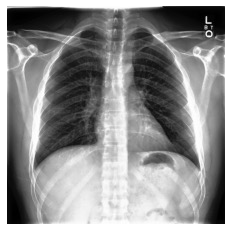

Automated diagnosis prediction from medical images is a valuable resource to support clinical decision-making. However, such systems usually need to be trained on large amounts of annotated data, which often is scarce in the medical domain. Zero-shot methods address this challenge by allowing a flexible adaption to new settings with different clinical findings without relying on labeled data. Further, to integrate automated diagnosis in the clinical workflow, methods should be transparent and explainable, increasing medical professionals' trust and facilitating correctness verification. In this work, we introduce Xplainer, a novel framework for explainable zero-shot diagnosis in the clinical setting. Xplainer adapts the classification-by-description approach of contrastive vision-language models to the multi-label medical diagnosis task. Specifically, instead of directly predicting a diagnosis, we prompt the model to classify the existence of descriptive observations, which a radiologist would look for on an X-Ray scan, and use the descriptor probabilities to estimate the likelihood of a diagnosis. Our model is explainable by design, as the final diagnosis prediction is directly based on the prediction of the underlying descriptors. We evaluate Xplainer on two chest X-ray datasets, CheXpert and ChestX-ray14, and demonstrate its effectiveness in improving the performance and explainability of zero-shot diagnosis. Our results suggest that Xplainer provides a more detailed understanding of the decision-making process and can be a valuable tool for clinical diagnosis.